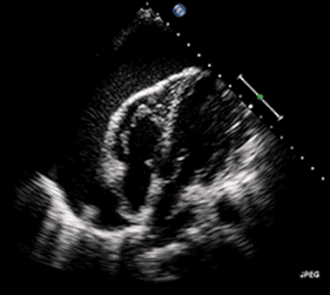

- Ecocardiograma

A sensibilidade diagnóstica do ecocardiograma é bastante elevada e quantidades tão pequenas como 20 ml de líquido pericárdico podem ser detectadas. Embora a quantificação do derrame pericárdico à ecocardiografia não seja exata, uma avaliação semiquantitativa (leve, moderado e grande) geralmente é possível e útil para a abordagem terapêutica. A localização do derrame é outro ponto importante, até mesmo para orientar o local de penetração da agulha ao se fazer pericardiocentese.

As características ecocardiográficas que acompanham o derrame pericárdico (presença ou ausência de traves de fibrina e aderências) e os folhetos pericárdicos (infiltrados, espessados, calcificados, com ou sem deslizamento adequado entre eles) podem ser importantes dos pontos de vista etiológico e terapêutico.